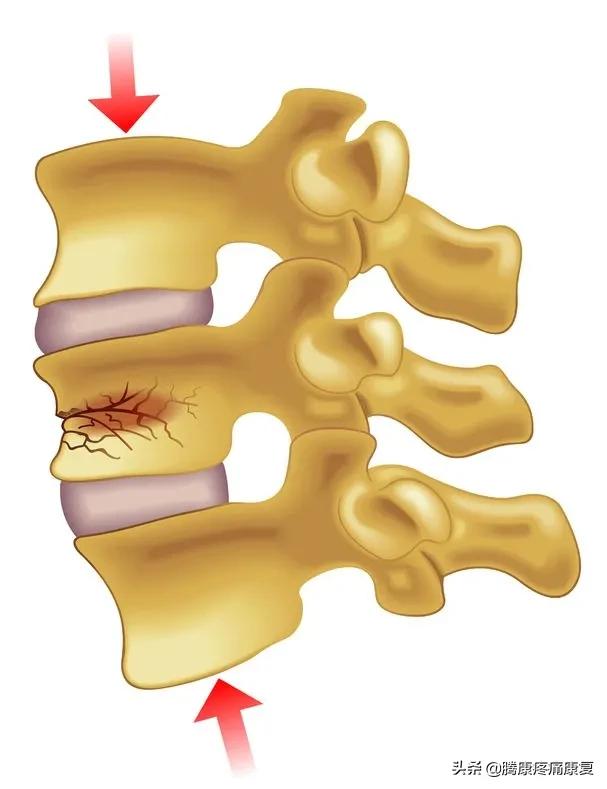

椎体压缩性骨折:

压缩性骨折通常是由骨质疏松症引起的,骨质疏松症是骨骼和关节的退行性疾病。压缩性骨折可导致胸椎和腰椎间盘高度降低,导致平背综合征。